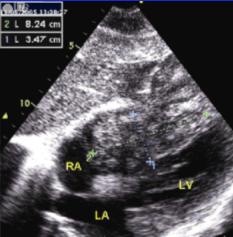

2、透析治療對終末期糖尿病腎病目前比較理想的治療措施是同時進行胰、腎移植,但限於各種條件只有很少的病人能得到這種治療,而多數終末期糖尿病腎病人,只能接受透析治療以延長生命。糖尿病腎病透析治療目前主要有2種方式,即長期血透和不臥床持續腹膜透析(CAPD)。

(1) 長期血透:從20世紀60年代初期就已開始對晚期糖尿病腎病病人套用透析治療,近年來接受血透者有所增加。如1972年還不到0.5%,1981年上升到7.3%,根據1988年美國統計因糖尿病腎病腎功能衰竭接受血透者約為新血透病人的28%。但由於終末期糖尿病腎病除腎臟病變外,幾乎同時都合併有其他器官的血管合併症,特別是由於全身性小動脈硬化,血管壁僵硬,血透的血管通道難以建立,動靜脈瘺管在糖尿病人保留的時間明顯短於非糖尿病人。因此,糖尿病腎病病人血透的存活率,儘管過去10年有了改善,但仍低於非糖尿病人,據Matson與Kjellstrand對369例長期血透病人的隨訪分析,3年累積存活率為45%,5年25%,10年為9%,年齡在60歲以下的1型糖尿病腎病病人血透的存活率20世紀80年代較之60年代有了明顯的提高,1年存活率由60%上升為85%,3年存活率由30%上升為60%,5年存活率由12%上升到45%。但Jacobs等報導歐洲1098例第1年存活率為67%,第2年為49%。1型糖尿病血透病人的死亡率幾乎為非糖尿病人的2.5~3倍,死亡原因仍以心血管合併症為主占51%,其次為中止透析占24%,感染占14%,其他如電解質紊亂(高鉀或低鉀)、高滲性昏迷等約占11%。血透的預後與糖尿病類型有關,1型病人的存活時間明顯短於2型病人,但2型病人有心血管合併症者存活時間短;病人年齡>60歲者預後差,60歲以下則差別不大;至於是否合併有糖尿病視網膜病變對預後關係不大。

糖尿病性腎病3、腎或胰-腎聯合移植對終末期糖尿病腎病病人,腎移植是目前有效的治療方法,在美國約占腎移植病人的20%,歐洲稍低,約占11%。從1969年開始對終末期糖尿病腎病病人行腎移植,最初的報導用屍體腎移植2~3年的存活率與非糖尿病人相似,1978年以前的2年存活率僅54%,比單純透析治療的存活率74%為低。近年來,糖尿病腎移植有了很大改進,特別是自採用環孢素(cyclosporine)作為主要抑制劑以來,5年存活率屍體腎移植為79%,活體